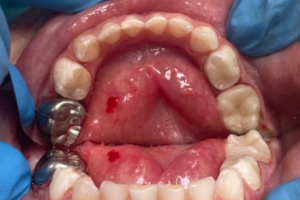

Семейная областная стоматология "Кидди Дентал" - это команда компетентных врачей, каждый из которых знает и любит свое дело. Опыт наших врачей, использование современного оборудования и надежных материалов позволят проводить лечение любой сложности.